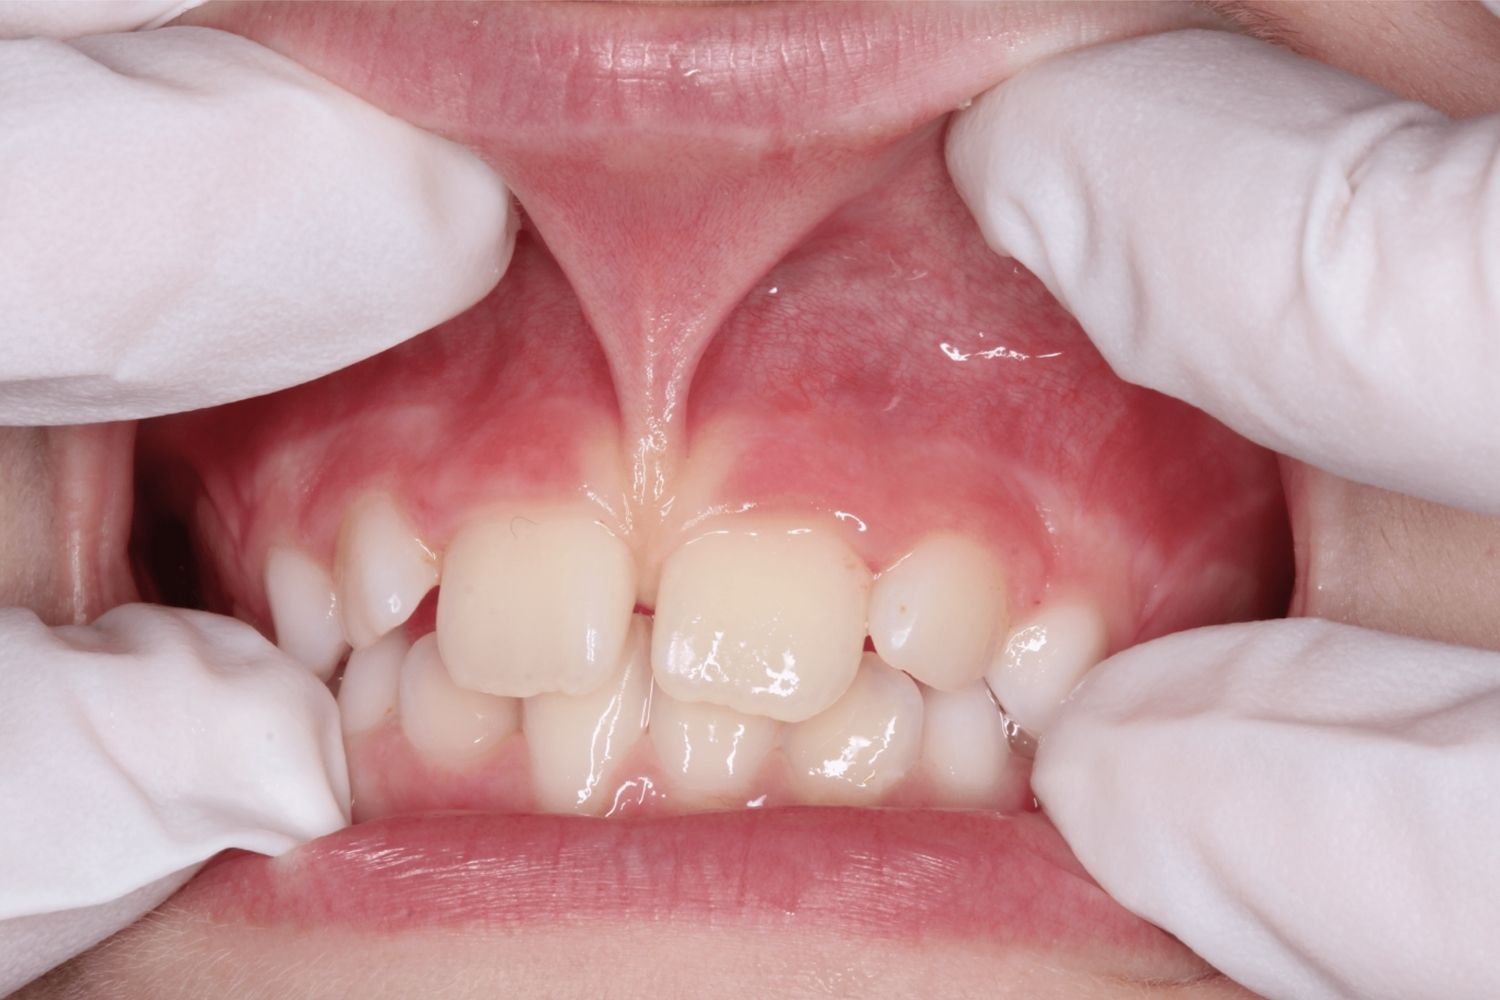

- A tight labial frenum can cause a gap between the front teeth, which may require a labial frenectomy.

- A labial frenectomy removes the frenum connecting the upper or lower lip to the gums, which can help with orthodontic issues.